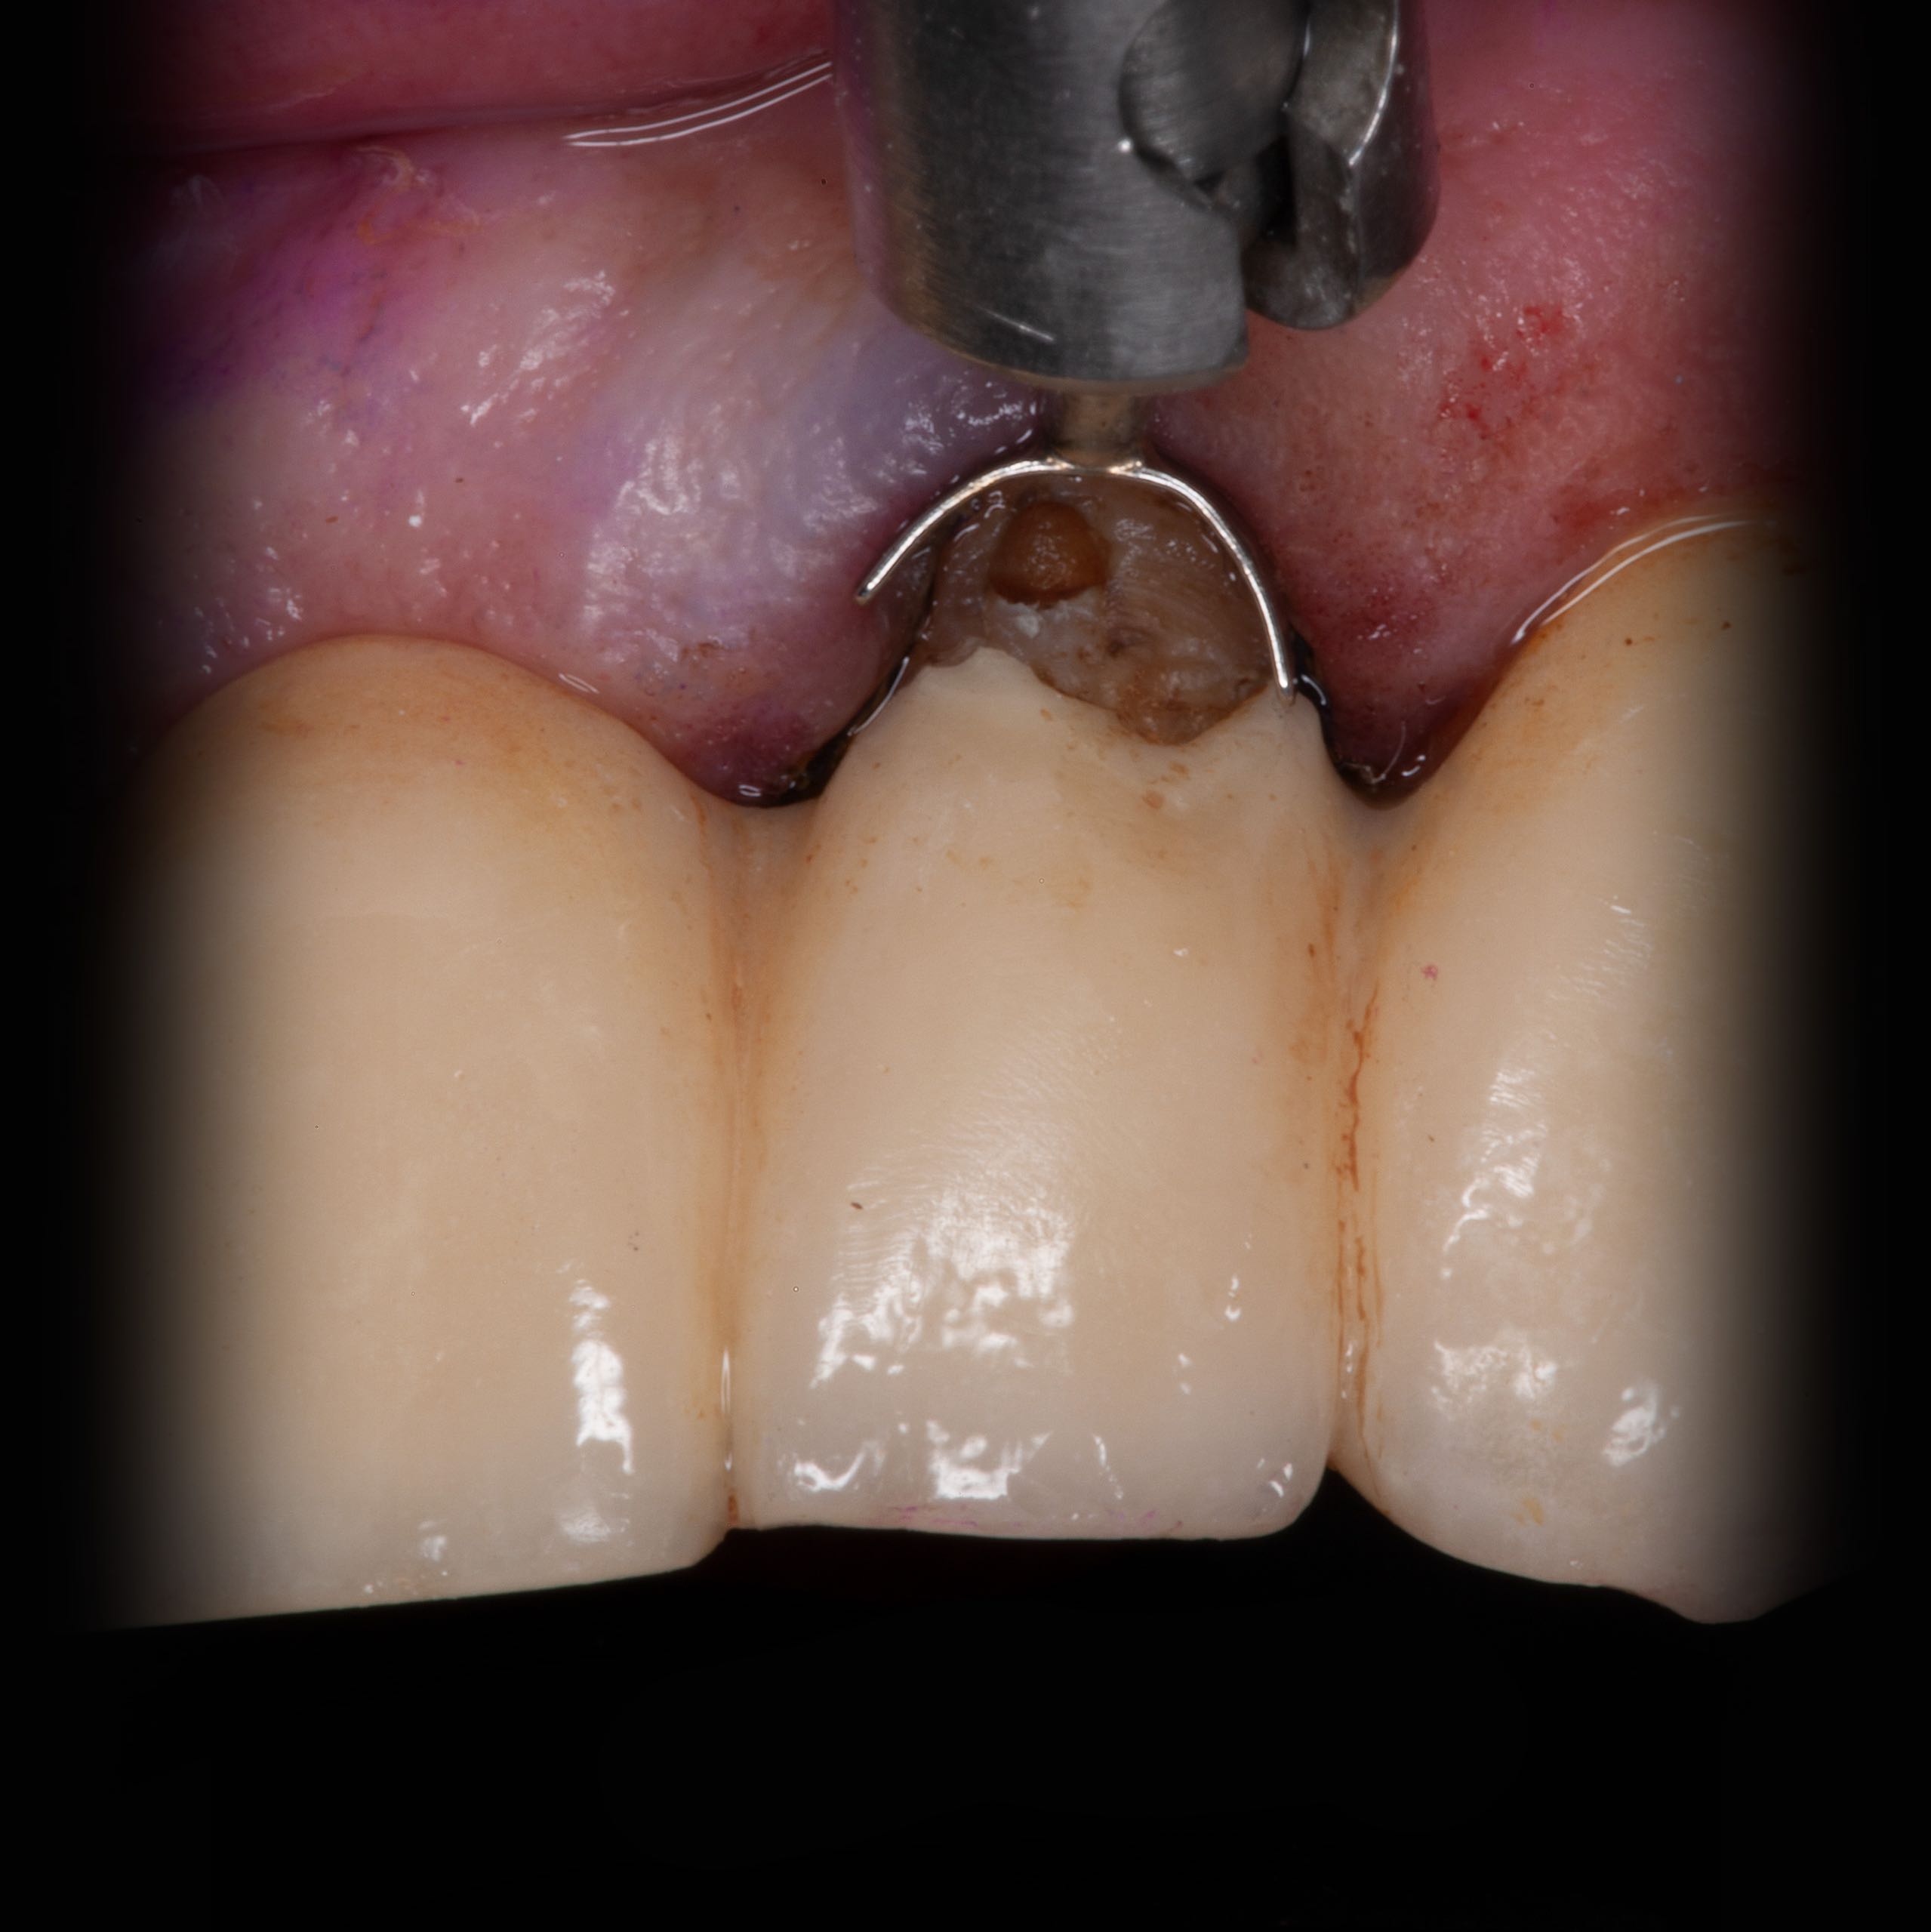

Bei Behandlungsbeginn

• Keramikfraktur mit Reparaturversuch

• iatrogenes Anbohren des Zahnes

• Knochendefekt bis zur Wurzelspitze, vorherige Wurzelspitzenresektion, unklare Wurzelfüllung

• Kontrolle auf Zahnfraktur

• Defektreparatur am Zahn und Keramik mit modernen Adhäsivsystem und Komposit-Konststoffen

Reparatur und Wiederherstellung der Krone am linken seitlichen Schneidezahn